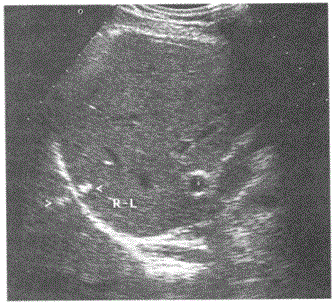

请指出下图箭头所指是何种声像图伪像:A.旁瓣伪像B.多重反射C.镜面伪像D.混响伪像

问题 请指出下图箭头所指是何种声像图伪像:

选项 A.旁瓣伪像 B.多重反射 C.镜面伪像 D.混响伪像

答案 C